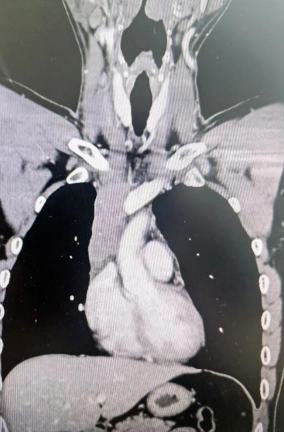

經(jīng)檢查發(fā)現(xiàn)患者前上縱隔腫瘤已經(jīng)完全侵犯了我們?nèi)梭w最主要的大靜脈之一——上腔靜脈,導(dǎo)致上腔靜脈回流嚴(yán)重受阻并導(dǎo)致由上腔靜脈起至左側(cè)無(wú)名靜脈、右側(cè)鎖骨下靜脈、右側(cè)頸內(nèi)靜脈等多根自上往下回流的靜脈阻塞,從而形成了廣泛的栓子,牢牢堵住了要流回心臟的血流,只能靠別的一些側(cè)支循環(huán)超負(fù)荷的工作,這也就是為什么孫先生脖子甚至是頭都明顯腫起來(lái)的原因。

4月30日,麻醉完成后,縱劈胸骨顯露右上縱隔腫瘤,發(fā)現(xiàn)腫瘤侵入上腔靜脈起始部,右鎖骨下靜脈及右頸內(nèi)靜脈血栓形成并向遠(yuǎn)端延伸。劉志主任團(tuán)隊(duì)將切口向右頸部延長(zhǎng),顯露右側(cè)頸內(nèi)靜脈至下頜角水平。張金洲副院長(zhǎng)團(tuán)隊(duì)經(jīng)股動(dòng)靜脈和左無(wú)名靜脈建立體外循環(huán)。在阻斷左無(wú)名靜脈遠(yuǎn)端后,李文海副院長(zhǎng)團(tuán)隊(duì)完整切除縱隔腫瘤及部分上腔靜脈、左無(wú)名靜脈、右鎖骨下靜脈和右頸內(nèi)靜脈切除。張金洲副院長(zhǎng)團(tuán)隊(duì)實(shí)施了無(wú)名靜脈近端、右鎖骨下靜脈和右頸內(nèi)靜脈內(nèi)血栓取出術(shù),并完成了左無(wú)名靜脈、右頸內(nèi)靜脈和右鎖骨下靜脈的人工血管置換手術(shù)。歷時(shí)6小時(shí),三個(gè)外科團(tuán)隊(duì)在麻醉科柴偉主任團(tuán)隊(duì)、體外循環(huán)團(tuán)隊(duì)以及食管超聲和手術(shù)室協(xié)作下,手術(shù)獲得成功。

術(shù)后患者經(jīng)過(guò)心外監(jiān)護(hù)室和胸外監(jiān)護(hù)室的接力治療,目前患者恢復(fù)順利,顏面部腫消失。復(fù)查增強(qiáng)CT三條人工血管通暢。